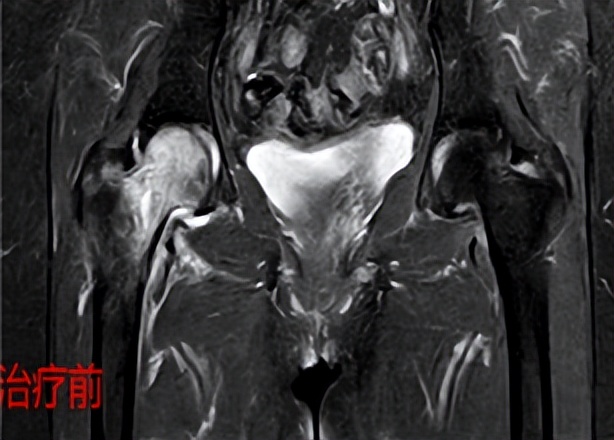

股骨头水肿综合症

患者孙某,女性,65岁,1个月前出现右下肢疼痛,伴有活动受限并有放射痛,到当地医院多方求治都考虑腰椎间盘突出症,给予对症治疗,但孙某右下肢疼痛不见好转,反而逐渐加重,夜间疼痛严重时无法入睡,生活痛苦不堪,家属经多方打听找到骨病·骨肿瘤科I王顺利主任,经过详细细微的查体,王顺利主任发现患者右髋部疼痛、活动受限明显,并伴有右下肢放射痛,结合患者已有的影像学检查,考虑股骨头病变引起,给予办理入院手续后,完善髋关节MRI检查后,果不其然是右侧右侧股骨头坏死、股骨头水肿综合征,结合患者年龄大,有高血压、冠心病等内科疾病,采用综合保守治疗,并应用体外聚焦式冲击波治疗,在应用冲击波治疗两次后,右髋部及右下肢疼痛,用孙某的话“奇迹般不疼了”,右髋部活动度恢复,患者及家属都非常感激王主任。一个多月没有看好的疼痛,来到郑州市骨科医院骨病·骨肿瘤科I,治疗两天后,疼痛就好了,非常高兴。王主任再次叮嘱患者,虽然目前疼痛缓解,但疾病还没有好,需要继续治疗,后面经过三个疗程的冲击波治疗,患者孙某右下肢疼痛消失了,恢复行走。